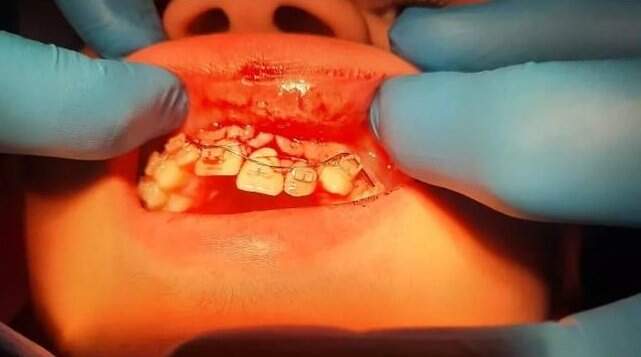

Um adolescente de 13 anos teve quatro dentes e a mandíbula quebrados após ser agredido dentro da Escola Estadual Fernando Lobo, em Juiz de Fora. Em nota, a Secretaria Estadual de Educação (SEE-MG) confirmou o caso e informou que o mesmo ocorreu na última quinta-feira (5) e que todas as providências foram tomadas.